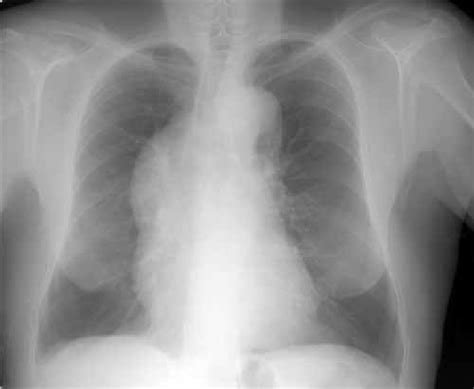

- Radiografía de tórax: Puede mostrar ensanchamiento mediastínico superior (hallazgo más frecuente), masa hiliar o derrame pleural.